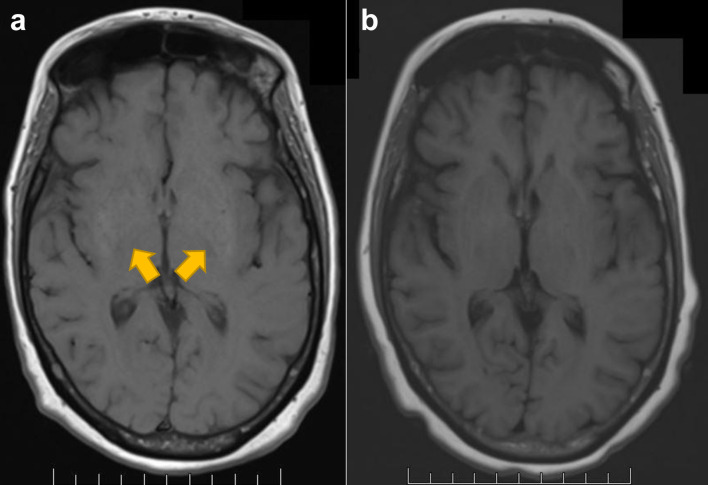

After ciltacabtagene autoleucel (cilta-cel) in multiple myeloma, 5% of patients can develop parkinsonism, with a high fatality rate. The pathogenesis and optimal therapy of parkinsonism from B-cell maturation antigen chimeric antigen receptor T-cell (CAR T-cell) therapy are unknown. Parkinson's disease occurs from the loss of dopaminergic neurons in the substantia nigra. However, in cilta-cel-associated parkinsonism, dopamine transporter imaging is normal, rendering traditional agents such as carbidopa/levodopa ineffective. Thus, the pathogenesis of cilta-cel-associated parkinsonism and Parkinson's disease is distinct. As CAR T-cell therapy for multiple myeloma is expanding and moving to earlier lines, the need to optimize therapy for parkinsonism, a potentially life-threatening complication, becomes more urgent. This report presents the first documented cases of two patients with immune effector cell-associated hemophagocytic lymphohistiocytosis-like syndrome and cilta-cel-associated parkinsonism, effectively treated with ruxolitinib.

Abstract Image